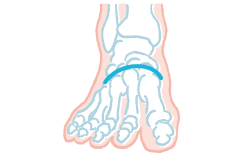

50歳を超えたあたりから

崩れやすくなる足のアーチ

かかとと小指のつけ根を結ぶ、縦に伸びるアーチ

かかとと親指のつけ根を結ぶ、縦に伸びるアーチ

5本の指のつけ根を結ぶ、横に伸びるアーチ